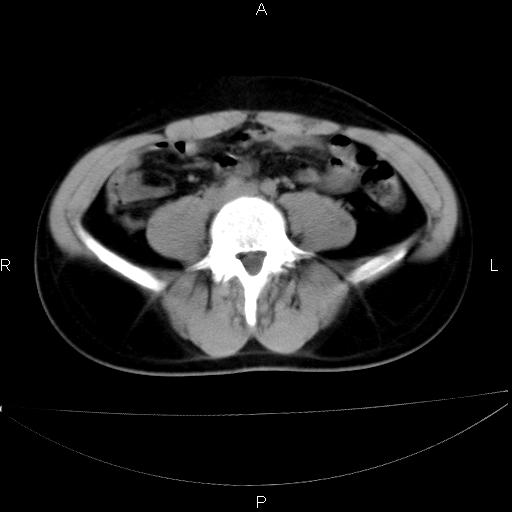

男 25岁 自述 尿频尿急,排尿困难20多天.无腰痛, b超说左肾盂轻度积水,左输尿管上端扩张.未见结石影. ct我看双侧肾盂轻度积水,双输尿管上端都扩张,大家看看能看见结石吗?

双肾轻度积水,双侧输尿管上段扩张(原因待查)。

双输尿管扩张下端未见高密度结石和输尿管晕轮征,不好说是结石.增强后如何?

双肾盂及双输尿上段轻度积水,双输尿管未见明显结石影。